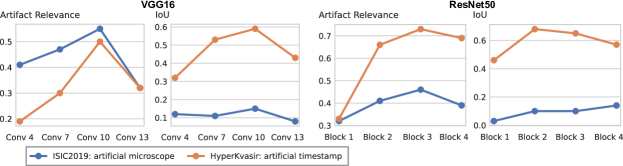

In this section, we leverage latent bias representations, either via directions or individual neurons, to retrieve biased samples and measure how well bias samples are separated from clean samples. We compute bias scores as defined in Eq. 1 by projecting latent activations onto the bias direction. As we are mostly interested in the ranking capabilities, i.e., artifact samples should be assigned higher bias scores than clean samples, we measure Area Under the Receiver Operating Curve (AUROC) and Average Precision (AP), considering both real and controlled artifacts. For real artifacts, we evaluate retrieval using existing artifact labels, while we have ground truth information for controlled experiments. We train CAVs using Support Vector Machines (SVMs) on different layers of VGG16 and ResNet50 models for all datasets, reporting AUROC and AP on unseen test samples. Note, that while Pahde et al. [58] claim that classifier-based CAV computation can yield imprecise concept directions, they argue that SVM-CAVs are superior for predicting concept presence, the main goal of this experiment. In Fig. 7, we show the results for different layers of VGG16 and ResNet50 using single neurons (dashed line) and CAVs (solid line) as bias representation. Best neurons are selected using the validation set. The results indicate that CAVs generally outperform single neuron representations for sample retrieval, and the layer choice is crucial depending on the bias type. For instance, while CAVs for layers closer to the model heads can detect pacemaker samples, they fail for earlier layers.

6.4 Spatial Bias Localization

To spatially localize biases in input space with CAVs, we compute local explanations for the element-wise product of latent activations and concept direction (see Eq. 2). We use the controlled artifacts, specifically timestamp (HyperKvasir) and micropscope (ISIC2019) with ground truth concept localization masks for evaluation. We compute (1) the percentage of relevance within the ground truth mask and (2) the Jaccard index, or Intersection over Union (IoU), of the binarized localization mask with the ground truth. In Fig. 9, we report both metrics using CAVs computed on different layers of VGG16 and ResNet50. The layer choice for concept representations is key, as for example middle layers perform better to localize timestamps and earlier layers are more effective to localize the microscope. In comparison with Fig.7, we find that the optimal layer for bias localization may differ from the one for sample retrieval. Interestingly, the IoU for the microscope artifact is consistently low, as models primarily focus on the border of the circle instead of the entire area, as indicated by qualitative results in Appendix A.6.3. Unlike artifact relevance, the IoU metric also measures how much of the expected areas the computed mask does not cover.